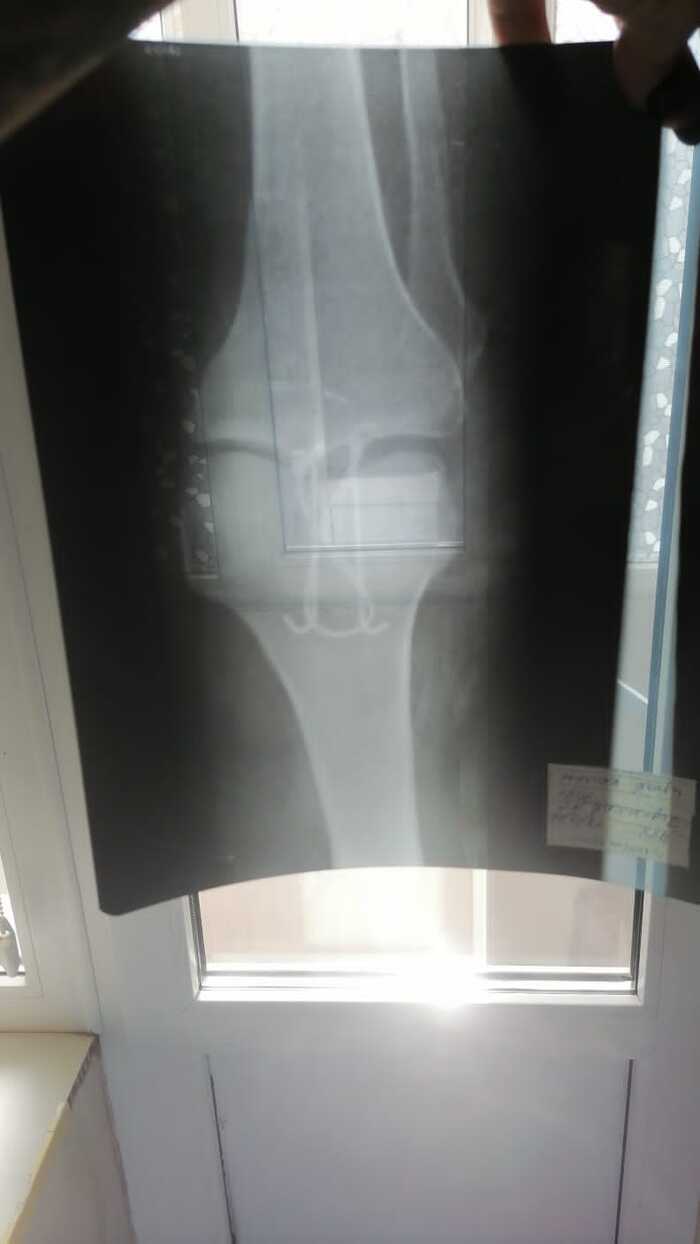

В начале марта 09.03.22 упал и в результате получил перелом надколенника. Была проведён остеосинтезе по Веберу 15.03.22. Нужна консультация в плане того когда можно давать нагрузку на ногу без сгибания в колене. От этого зависит как быстро смогу начать ходить и выйти на работу, так как на один больничный семью просто не вытяну. Информация от лечащего врача противоричивая: то можно давать нагрузку то нельзя.